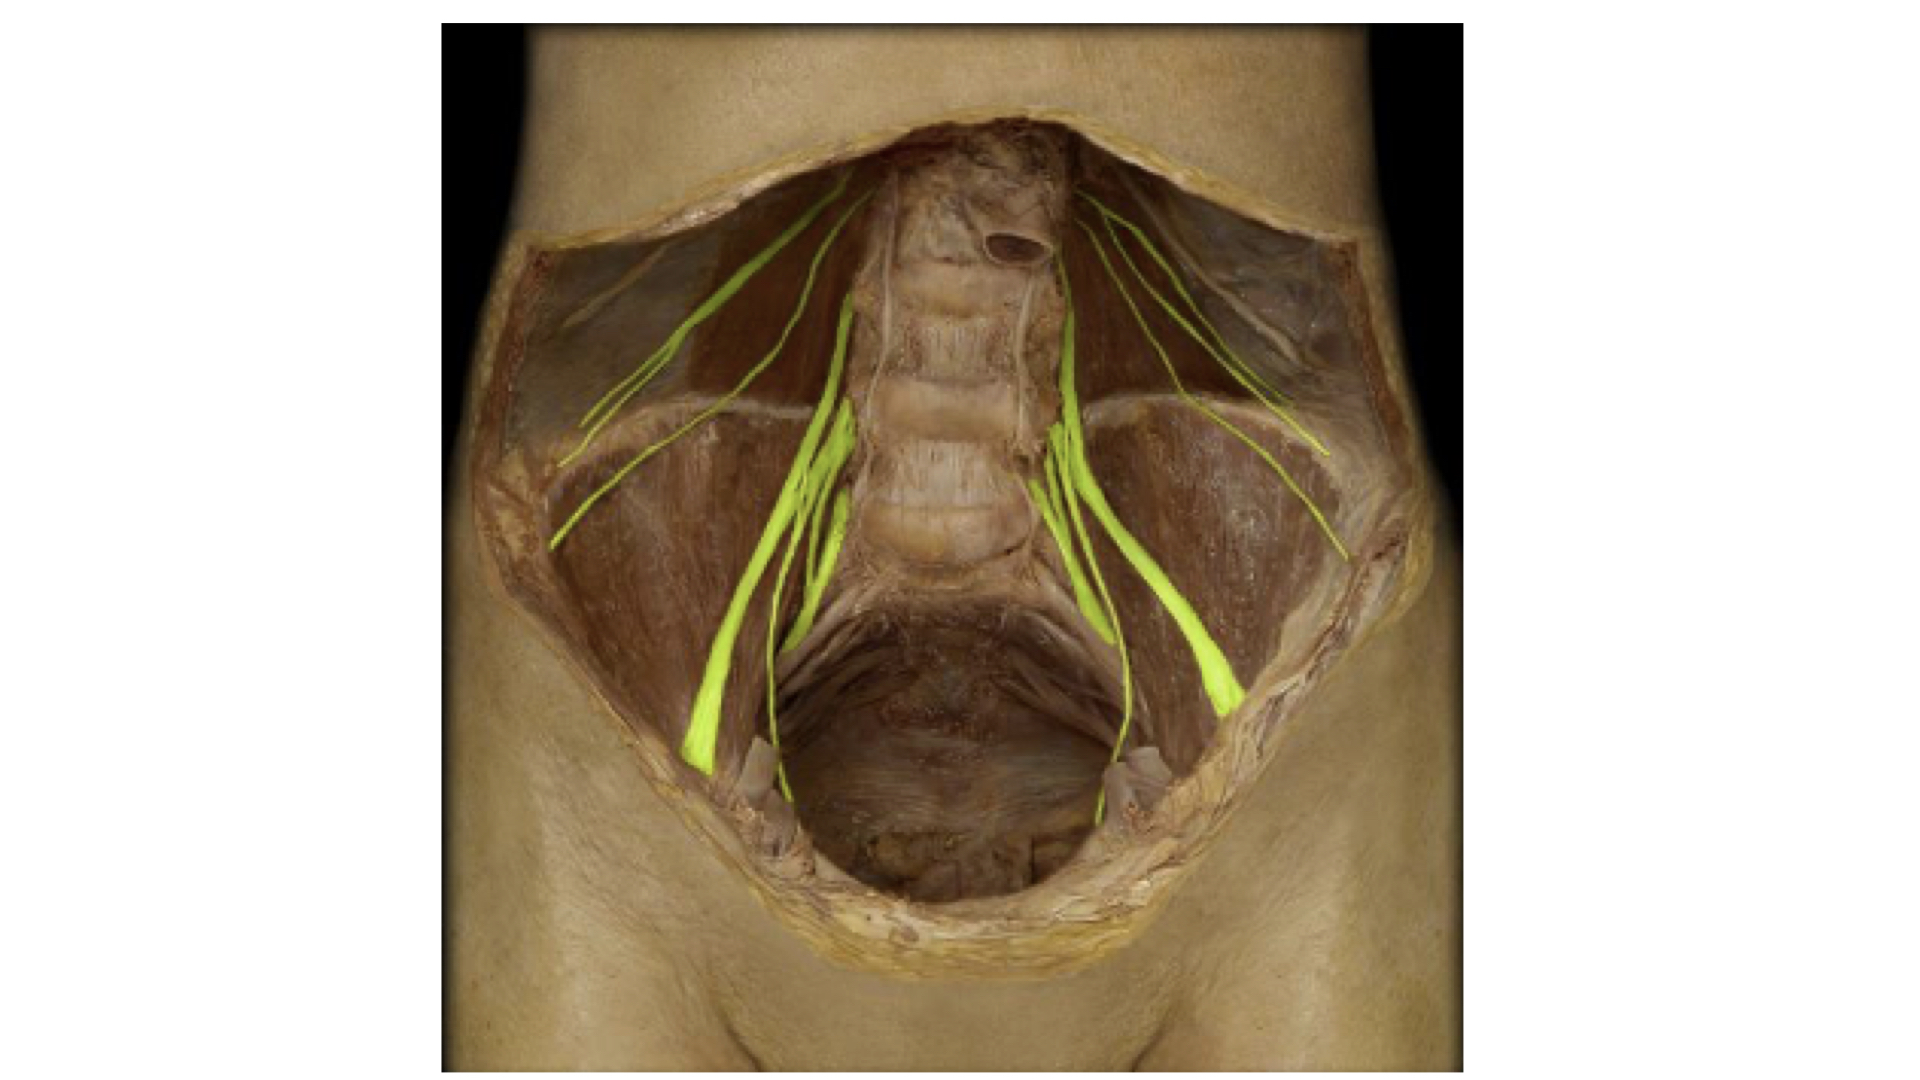

d. Lumbar Plexus. The major nerve from this plexus is the femoral.

Lumbar Plexus with Femoral Nerve Highlighted.

Lumbar Plexus with Femoral Nerve Highlighted.